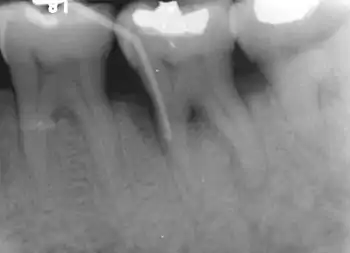

Furcation defect

In dentistry, a furcation defect is bone loss, usually a result of periodontal disease, affecting the base of the root trunk of a tooth where two or more roots meet (bifurcation or trifurcation). The extent and configuration of the defect are factors in both diagnosis and treatment planning.[1]

Nabers probe is used to check for furcation involvement clinically. Recently, cone beam computerised technology (CBCT) has also be used to detect furcation.[5] Periapical and interproximal intraoral radiographs can help diagnosing and locating the furcation.